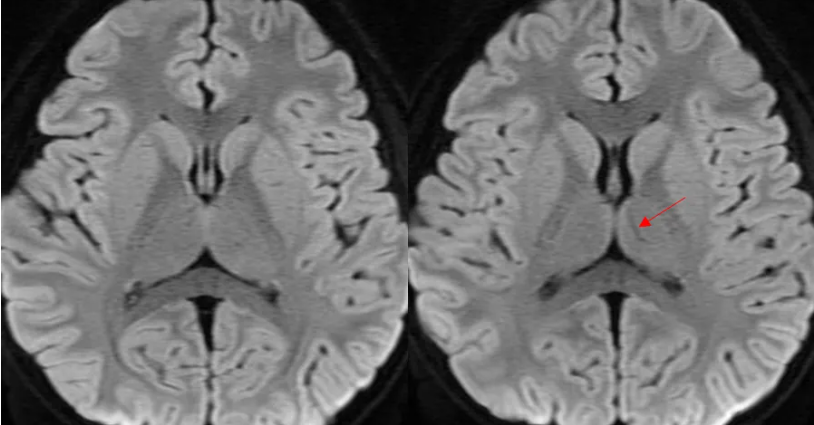

常规序列,好像并没有发现到什么异常信号。

除了

DWI低信号,ADC高信号; DWI稍高信号,ADC略下降。 小朋友,你是否也有很多问号?